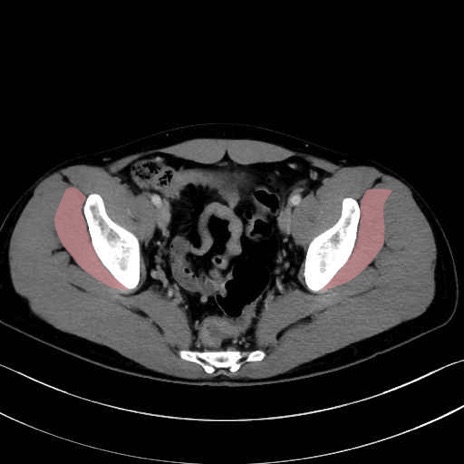

小殿筋 (Gluteus minimus)